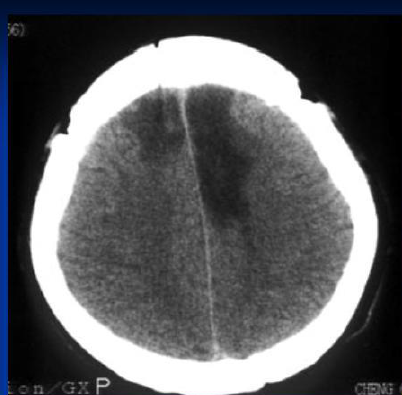

מהו הממצא ומה תיהיה התמונה הקלינית

A

חסימה של ACA משמאל

שיתוק ואיבוד תחושה ברגל ימין

תסמינים פרונטליים

**לרוב 2 העורקים יוצאים מאותו קרוטיד ולכן חסימה אחת תשפיע גם על השני